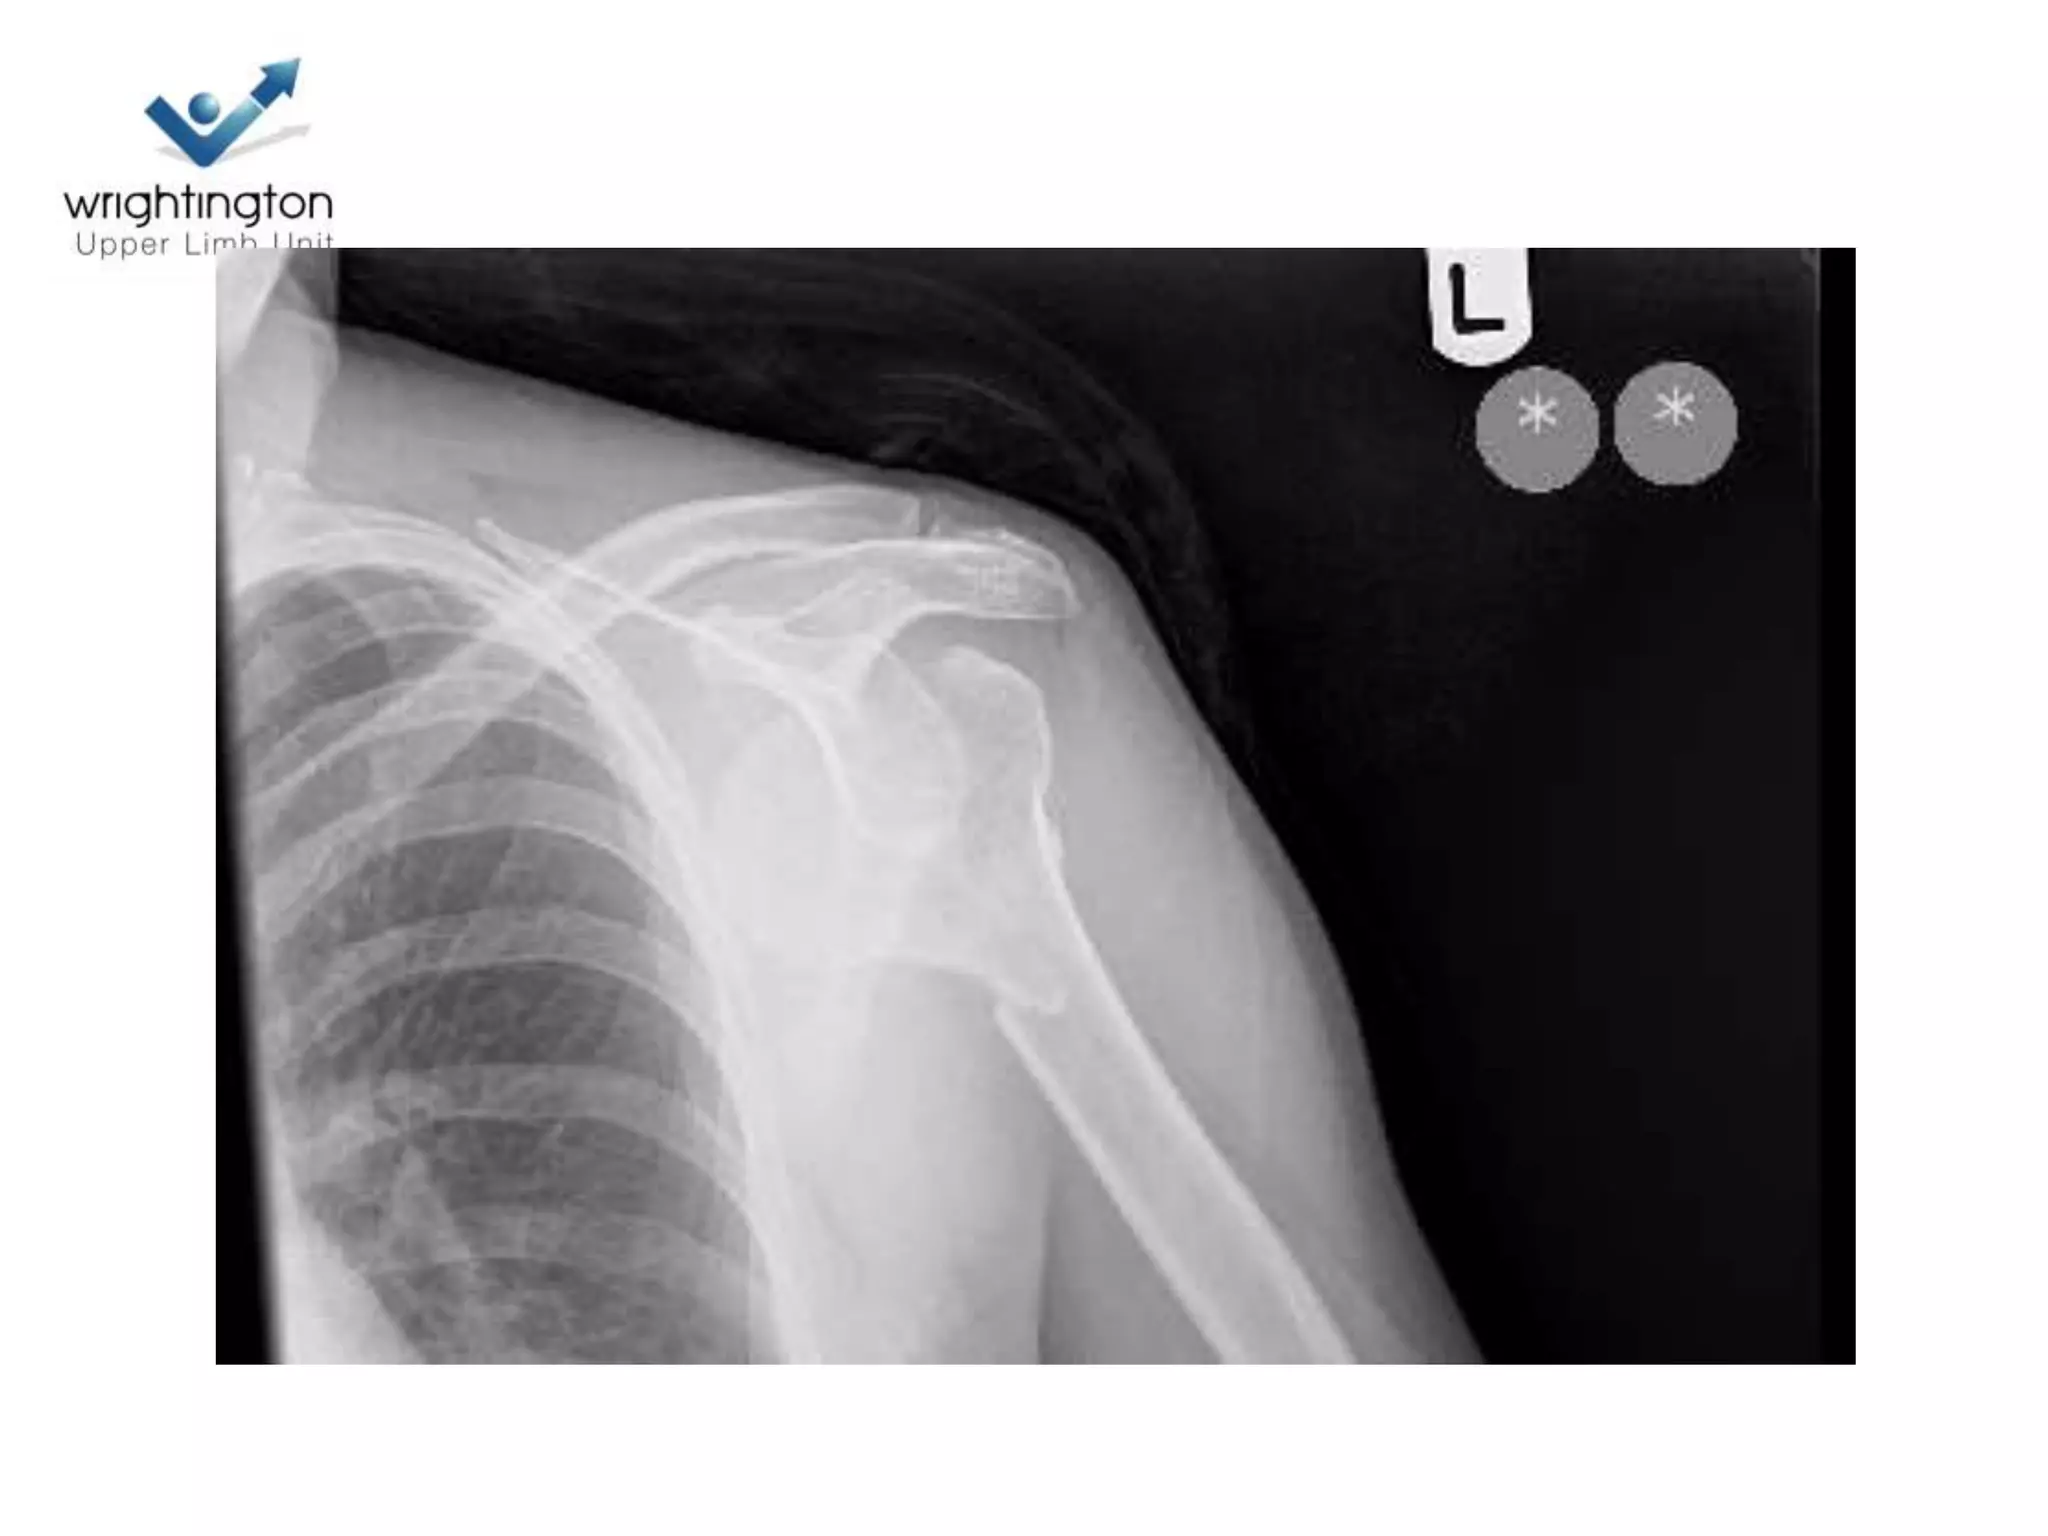

Case discussions

2 Next